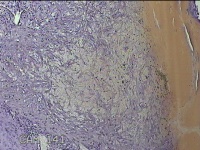

左卵巢囊肿

性别

女

年龄

47岁

临床诊断

左附件囊肿

一般病史

不规则阴道流血20余天。

标本名称

大体所见

灰白暗红色囊壁样组织4.3x1.3x0.3cm一块,表面光滑,因已切开,囊内容物已流失,囊壁厚0.1cm。

良性病变。